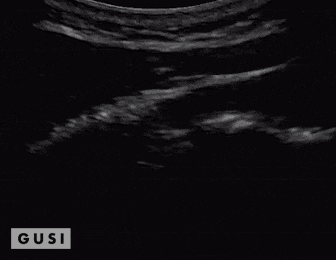

A 25-year-old male Taekwondo competitor from Africa experienced significant pain and tenderness in his right flank after receiving a forceful kick during the 2017 World Taekwondo Championships held in Muju, Korea. An immediate POCUS at the venue indicated a fracture in his 8th rib on the right anterior side of his chest.

A: The rib showed angular displacement in the longitudinal view.

B: In the transverse view, the rib appeared displaced.

C: Subsequent chest ultrasound scans did not detect a pneumothorax, and the athlete had no breathing difficulties with stable vital signs.

Initial on-site management was conservative, and the athlete later sought additional treatment from his sports doctor back home. His team’s physiotherapist confirmed the fracture through an x-ray during a subsequent check-up. He fully recovered in a few weeks without facing any setbacks.